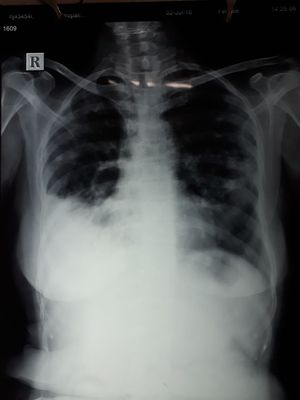

55 yr old female c/o rt sided chest pain cough dry type with fever off and on since 2 month.

Looks like severe pneumonia